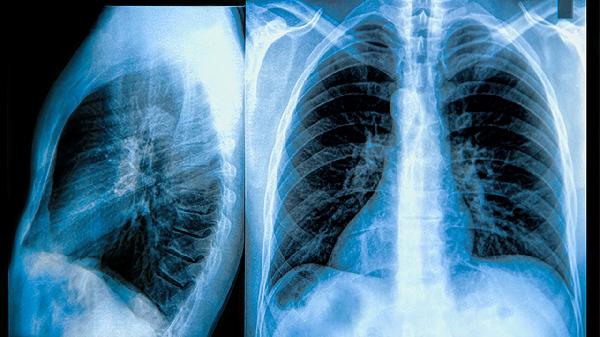

该综合征最常见于对化疗高度敏感的恶性肿瘤,如伯基特淋巴瘤、急性淋巴细胞白血病等血液系统肿瘤,也可见于转移性乳腺癌、小细胞肺癌等实体瘤。某些高危因素会增加发生概率,包括肿瘤负荷大、乳酸脱氢酶水平高、肾功能不全等情况。预防措施包括治疗前充分水化、使用别嘌醇或拉布立酶降低尿酸、密切监测电解质等。一旦确诊需立即静脉补液、纠正电解质紊乱,必要时进行血液透析。